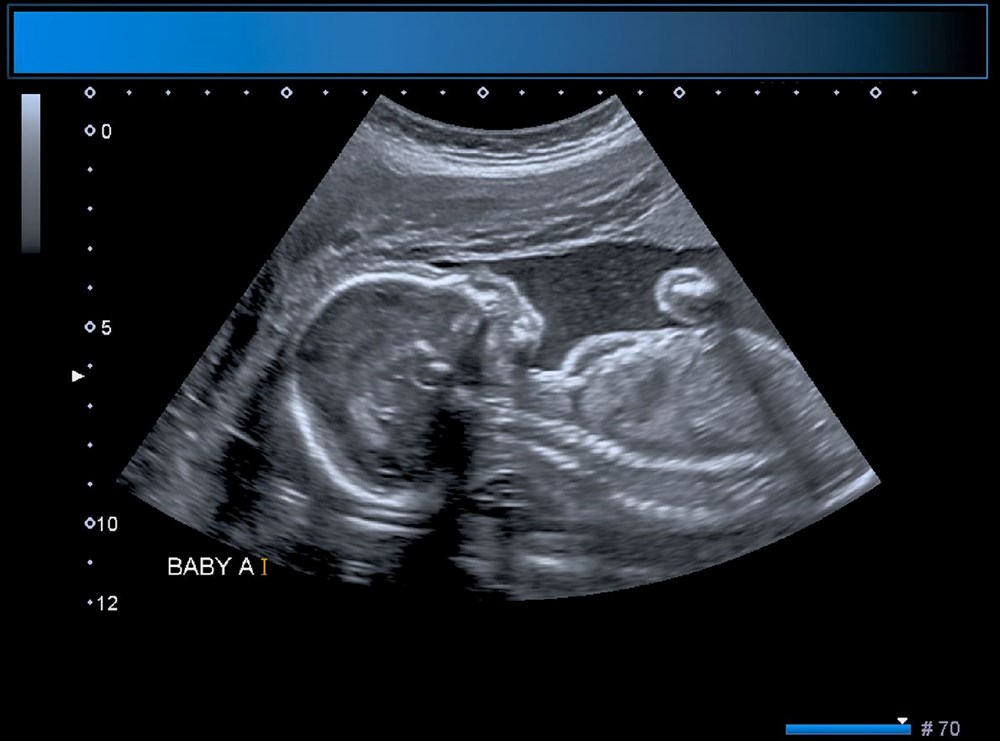

ABD'li doktorlar, türünün ilk örneği olan bir beyin ameliyatını çocuk henüz anne karnındayken gerçekleştirerek, doğmamış bir bebeği kesin ölümden kurtardı. Genetik bir bozukluk olan Galen damarı Malformasyonu'ndan (VOGM) muzdarip rahimdeki bebeğin kafatasını kesmeyi ve ardından gelişmekte olan beyni ameliyat etmeyi içeren titiz bir prosedür gerçekleştiren doktorlar, dünyada ilk kez yapılan operasyon ile birçok çocuğun hayatının kurtarılabileceğini müjdeledi.Türünün ilk örneği olan ve hayat kurtaran bir prosedürle anne karnındaki bir bebeğe beyin ameliyatı yapıldı.ABD'li doktorlar doğmamış çocuktaki ölümcül bir damar rahatsızlığını tedavi ederek doğumdan kısa bir süre sonra kalp yetmezliği ve felç geçirmesini önledi. Daha önce de rahimde beyin ameliyatı yapılmıştı, ancak Galen Damarı Malformasyonu (VOGM) adı verilen bu nadir hastalık için yapılmamıştı.Anneyi 34. haftada ameliyat eden bilim insanları, operasyonu yönlendirmek için ultrason kullandı. BEBEK SAĞLIKLI BİR ŞEKİLDE EVİNE DÖNDÜBoston Çocuk Hastanesi'nden Dr. Darren Orbach konuyla ilgili yaptığı açıklamada, "Genellikle doğumdan sonra görülen bebeğin sağlığındaki düşüşün ortaya çıkmadığını görmek bizi çok heyecanlandırdı. Şu anda altı haftalık olan bebeğin, ilaç kullanmadan, normal beslenerek ve kilo alarak eve döndüğünü bildirmekten memnuniyet duyuyoruz. Operasyonun beyin üzerinde herhangi bir olumsuz etki belirtisi yok." dedi. GALEN DAMAR FORMASYONU HAKKINDABununla birlikte, Galen Damar Malformasyonu (VOGM) her yıl yüzlerce bebeği etkiliyor ve çocuklar doğumun ilk birkaç gününden sonra hayatta kalamayabiliyor. Hastalık, beyindeki atardamarların kanı kılcal damarlar yerine doğrudan toplardamarlara akıtmasına neden olarak kalbin boğulmasına ve beyin hasarına yol açıyor.Mevcut tedaviler ise şimdiye kadar bebeğin doğumundan sonrası ile sınırlıydı, ancak bu noktada çoğu vakada beyin hasarı çoktan meydana gelmiş oluyordu. "Stroke" adlı bilimsel dergide sonuçları açıklanan yeni cerrahi operasyon, hastalığı bebeği etkilemeden önce iyileştirmeyi amaçlıyor.Diğer taraftan, operasyon kapsamında 10 sağlık görevlisinden oluşan bir ekip, annenin karnından uzun bir iğneyi bebeğin beyninin arterlerin etkilendiği kısmına yönlendirmek için ultrason kullandı. Doktorlar, daha sonra damarlara geri akışı engellemek için damar içine küçük bir madde enjekte etti.Dr. Orbach, "Bu yaklaşım, Galen Damarı Malformasyonu’nun tedavisinde büyük bir potansiyele sahip. Malformasyonu doğumdan önce onarıyoruz ve doğumdan sonra tersine çevirmeye çalışmak yerine kalp yetmezliğini ortaya çıkmadan önlüyoruz. Bu, bu bebekler arasında uzun vadeli beyin hasarı, sakatlık veya ölüm riskini önemli ölçüde azaltabilir." diye konuştu.